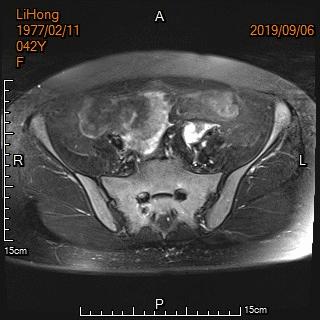

中年女性,反复痛经、经期延长5年余。确诊为子宫腺肌症,经妇科保守治疗症状无改善,病情进行性加重。

术前MRI显示子宫明显增大

术前MRI显示子宫明显增大,病灶主要位于子宫后壁